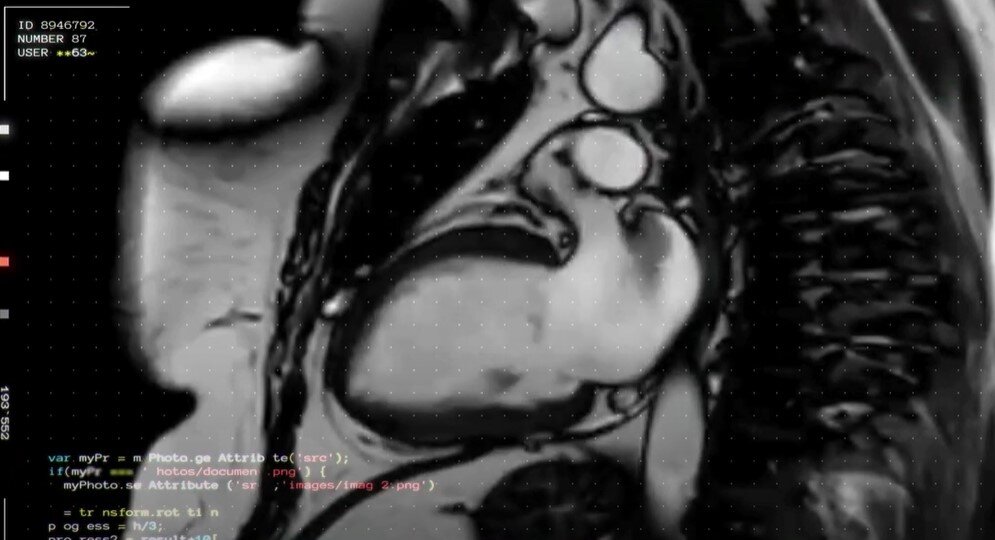

Когда анкета и согласие на обработку данных заполнены, вы сдаёте общий анализ крови, вам измеряют давление, рост и вес. Затем идёте в кабинет МРТ, где проходите обследование сердца. Потом, если вы написали в анкете, что курите, нужно будет пройти спирографию — определение объёма и скоростных характеристик дыхания. Если не курите, всё равно можете пройти дыхательный тест по желанию. И тут вас поджидает первый неприятный сюрприз.